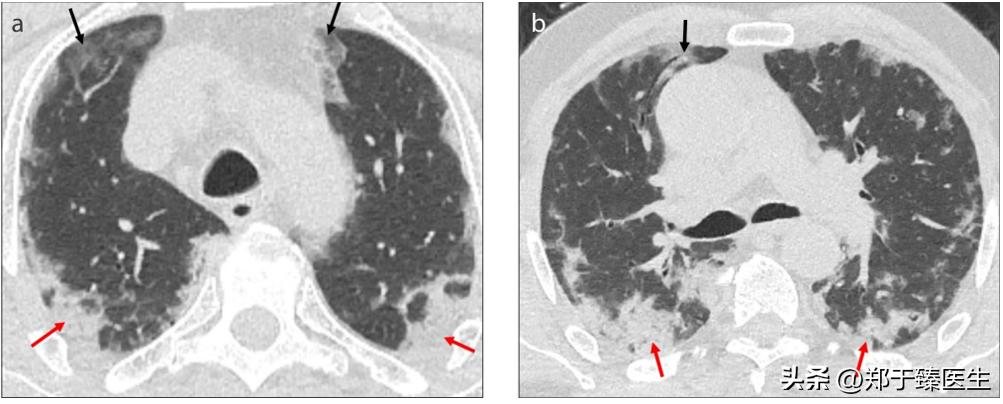

12月下旬,患者联系我,说自觉胸闷不适,我担心体内遗留肺炎情况,因此建议他复查了个CT(2022.12.25),结果一看,果然出现肺炎了。

于是,我尽快给他安排住到我们医院,在和主管医生沟通后,查了核酸阴性,于是就上了小剂量激素配合抗生素进行处理(2022.12.26开始)。

一周后,复查CT,炎症消退,患者症状明显好转,办理出院(2023.1.4)。

前后治疗周期10天。

从CT的片子来看,炎症几乎全部吸收,甚至连胸膜下线都没有看到,这说明实变区域吸收非常彻底,没有遗留任何纤维结缔组织,也就是没有任何后遗症。

下面就是治疗前后的CT改变: